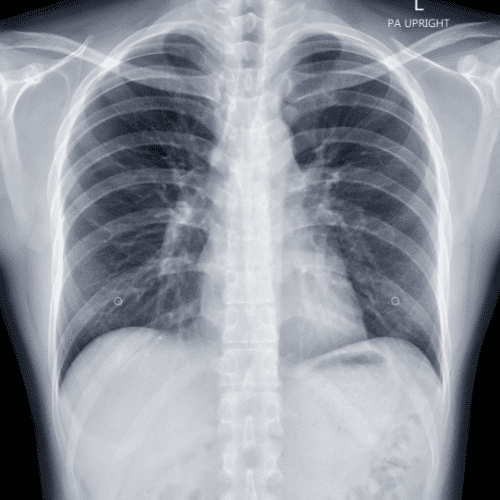

X-Ray

At Heal and Health Hospitals, our digital X-ray services provide fast, high-resolution imaging for accurate diagnosis. With a team of experienced radiologists and the latest equipment, we ensure safe and reliable imaging support for all departments.